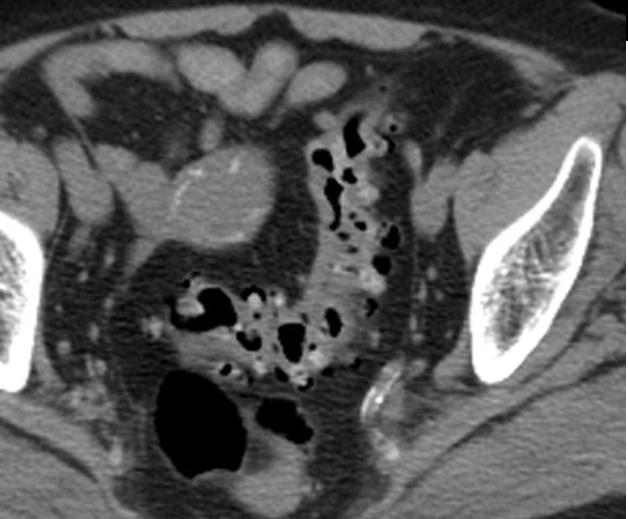

Aspect TDM du tuberculose ileocaecale est : Epaissisement

circumferentiel de la paroi ileum et caecum . Asymetrique

epaissisement de la valve ileocaecale .Mesenteric

lymphadenopathie et tuberculose pulmonaire est le plus

souvent .

Tuberculose ileo-caecale :

Image de epaissisement circumferentiele hyperdense

de ceacum avec lymphadenopathie mesenterique (

fleche rouge ). Image

TDM en coupe coronale |